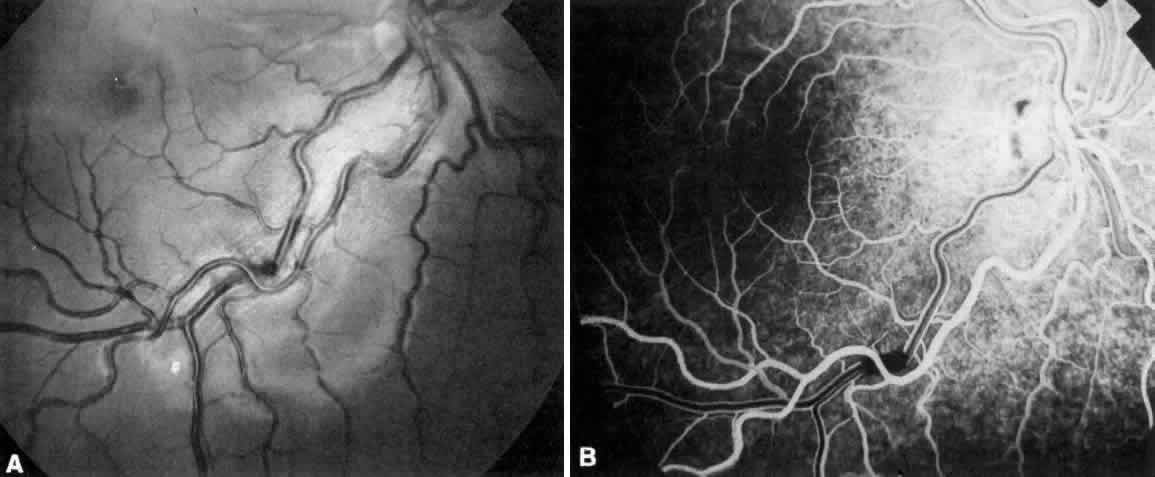

Cyanotic CHD when associated with severe hypoxemia and erythrocytosis may result in retinal and disc edema, as well as vascular (primarily venous) tortuosity.76 Severe erythrocytosis (hematocrit in the high 60s and greater than 70% may lead to severe vascular dilatation and tortuosity that mimics central retinal vein obstruction; retinal and disc edema may result (Fig. 1). Cerebral abscess occurring in this population may also be present with retinal and disc edema.

Fig. 1. A. Fundus photograph of cyanotic right retina demonstrating violaceous dilated retinal veins secondary to erythrocytosis. B. Fluorescein study of A.

Primarily arteriolar tortuosity is noted in patients who have aortic coarctation.77 Arteriolar constriction and arteriovenous crossing changes are rare in hypertensive patients who have aortic coarctation; hemorrhage and cotton-wool spots (retinal nerve fiber layer infarcts) are absent. Another feature of arteriolar tortuosity in patients who have aortic coarctation is the diffuse nature of the arteriolar tortuosity, perhaps resulting from wide pulse pressure; patients who have systemic hypertension from other causes generally have perimacular arteriolar tortuosity.